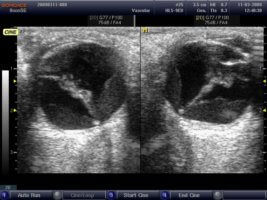

При включении аппарата и контакте детектора с кожей век врач получает черно-белое с различными оттенками серого цвета изображение исследуемой области на телевизионном мониторе, которые можно вывести на печать посредством принтера, подключенного к монитору аппарата.

В процессе диагностики врач может просить пациента двигать глазными яблоками для получения наиболее полной картины изображения. Изображение может выводиться в двух вариантах в зависимости от первоначальных настроек аппарата.

Позитивная регистрация определяет белый цвет участков, на которых наблюдалась наибольшая частота эхолокационных сигналов (эхопозитивные участки), и черный цвет эхонегативных участков с наименьшей частотой импульсов.

Негативная регистрация дает изображение с обратным расположением цветов. Выбор вида регистрации не влияет на результат исследования.

Выделяют три режима работы сканера: А, В, М.

- А-режим дает одномерное изображение, в котором одна координата является амплитудой отраженного импульса от границы сред с разной плотностью, вторая – расстоянием до этой границы.

- В-режим дает двухмерное изображение в масштабах реального времени.

- М-режим дает одномерное изображение, где одна координата – расстояние до границы сред, вторая – время отражения.